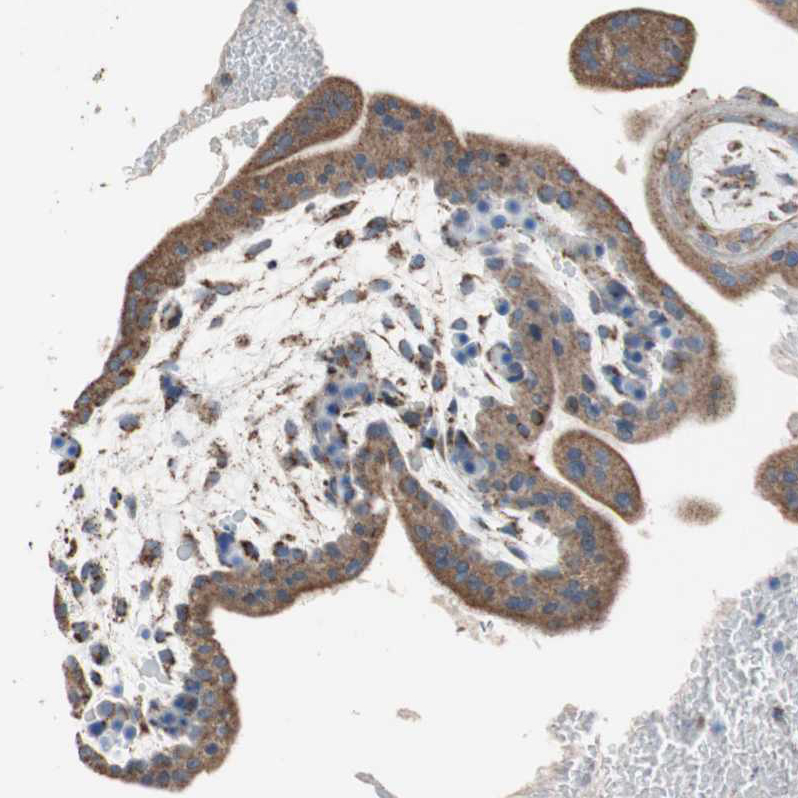

Immunohistochemical staining of human testis shows moderate granular cytoplasmic positivity in cells in seminiferous ducts and Leydig cells.